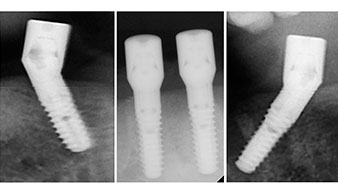

Направи се скенер с триизмерна компютърна томография (CBCT, Planmeca), за да се подпомогне планирането и да се намалят рисковете. Той показа, че качеството и количеството на наличната кост са достатъчни за операцията и имедиатното възстановяване, използвайки Fast & Fixed метод. Следвайки протокола за тази концепция, имплантите са поставени на 35, 32, 42 и 45 позиция. Ангулирането на дисталните импланти до 45° промени профила в задната зона и осигури по-голяма поддръжка в многоъгълната зона (Фиг. 3).

Ангулираните абатмънти (35°) са завити в имплантите, за да компенсират отклонението от дисталните импланти, така че в резултат профилът на разположение на всички импланти да е възможно най-перпендикулярен на нивото на захапката. Това е предпоставка за оклузално поставяне на временна и впоследствие на постоянна протеза (Фиг. 15 и 16).

Светлината увеличава контраста в оралната кухина и подобрява визуалното възприятие. Обратният наконечник и S-11 прав наконечник на W&H са с външно охлаждане, което е голямо предимство по отношение на физиологичния разтвор, който достига точно, където трябва и може да бъде впоследствие редуциран, ако е необходимо. Правите и обратни наконечници могат да бъдат разглобени, което е силно препоръчително от гледна точка на хигиената и стерилизацията. Поставени са четири импланта SKY с размери 4.0 x 14 мм.